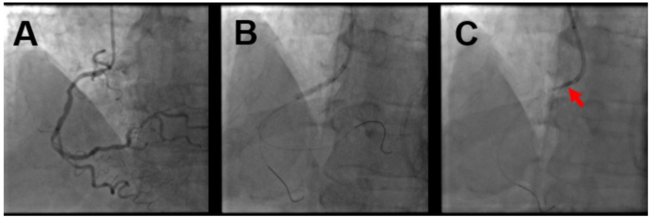

An 80-year-old man was admitted for acute coronary syndrome with ST elevation in the anterior leads. Primary percutaneous coronary intervention (PCI) was performed on the left anterior coronary artery by implanting 3 drug-eluting stents. After 48 hours, we planned PCI on severe stenosis of the ostial and proximal right coronary artery (RCA) (Figure 1A).

We engaged the RCA with a JR 4.0, 6-Fr sidehole guiding catheter through the right radial artery access and put 2 coronary guidewires in the distal RCA and acute marginal branch. We predilated the proximal and ostial lesions with a noncompliant balloon catheter (2.75 x 20 mm) with good angiographic expansion (Figure 1B). While advancing a 3.0 x 30-mm Resolute Onyx zotarolimus-eluting stent (Medtronic) through the RCA ostium, we noticed the sudden and complete dislodgment of the stent from the delivery balloon. As a result, approximately half of the stent was entrapped in the ostial-proximal RCA and the remaining proximal half extended back into the aorta (Figure 1C). Despite this, the patient remained asymptomatic and hemodynamically stable, with normal coronary flow and no electrocardiographic changes.